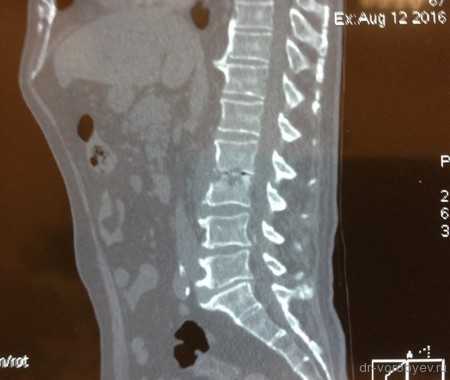

Рентген до операции